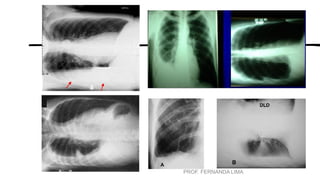

• •Identificar e contar os pares

de costelas.

• (O 1º e 2º pares são os mais

difíceis de localizar.)

• •Inspirar da maneira mais

profunda possível e então prender

a respiração de modo a aerar os

pulmões por completo.

• (Fazer uma segunda inspiração

profunda antes de prender a

respiração permite uma inspiração

ainda mais profunda)

• Observar o grau de

deslocamento

do diafragma para baixo

através da contagem dos

pares de costelas

projetadas acima

das cúpulas do

diafragma.

• Uma regra geral para a

média dos adultos

é “mostrar” um mínimo

de dez costelas no tórax

em PA ideal.